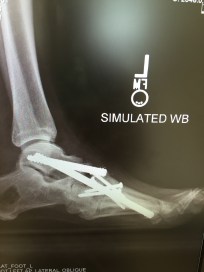

FootEngineeringThat could be the message for me as well. Right now, I’ve reached

FootSideView

Hardware – my own personal erector set

day seven on my hospital stay, which is quickly turning into day eight. On Friday, I had a fourth surgery; this time to remove hardware, which was cultured for bacteria. Unfortunately it has yielded a positive reading, which means I will need a PICC line inserted for at-home infusion of antibiotics. Although my surgeries have forced me to “slow down,” and I’ve tried to rest productively through all three set-backs, this time around, I’ll have to Wait and See  believing that, “he’s not finished with me yet…”